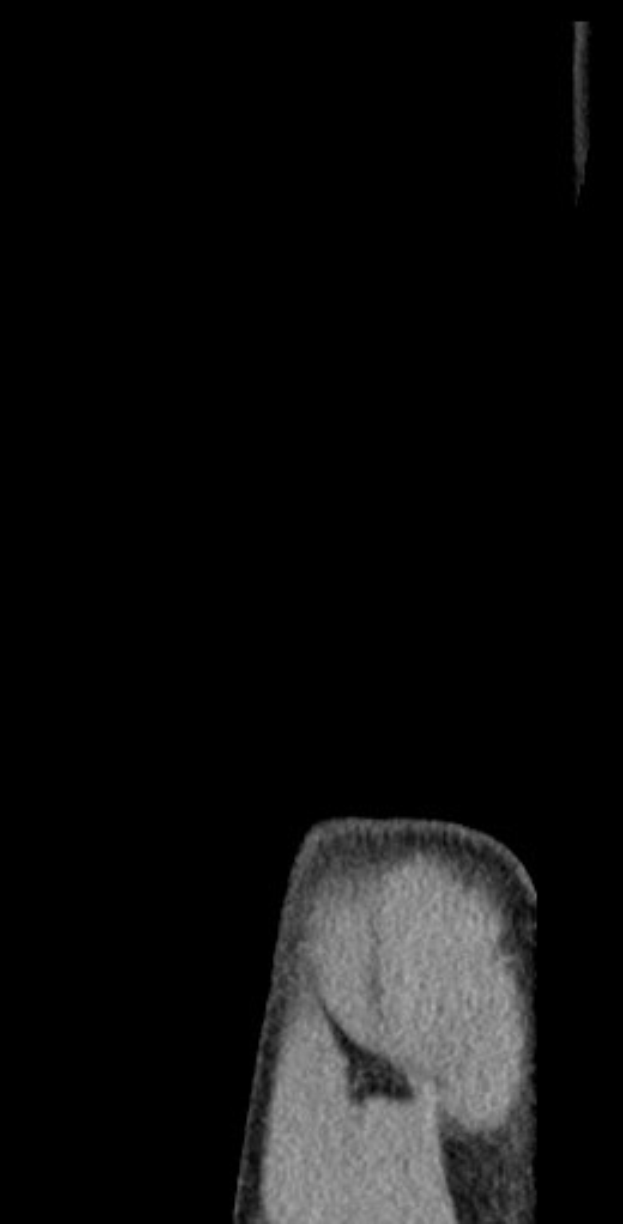

Gechter verließ das Feld mit Schmerzen in der Schulter, eine sofortige Diagnose stand zunächst aus. Der Club hat zur genauen Begutachtung des Verletzungsausmaßes eine MRT-Untersuchung angesetzt. Bereits in der vergangenen Saison hatte er mit einem ähnlichen Problem zu kämpfen, das ihn monatelang außer Gefecht setzte.